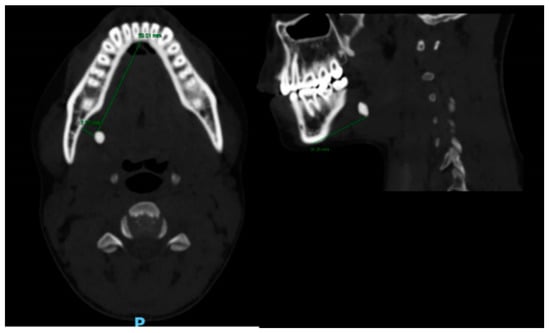

- Sialolith characteristics (according to CT)

- Size (Figure 1): length; width; height; volume (calculated by: length X width X height, we used the formula for a volume of a box as an approximation for the volume of the irregularly shaped sialoliths).

| Size(mm); | |

| Anterior-posterior (mean, SD) | 6.6 ± 4.2 |

| Superior-inferior (mean, SD) | 7.4 ± 4.6 |

| Lateral-lateral (mean, SD) | 5.2 ± 2.8 |

| Sialolith location (%); | |

| Gland | 12 |

| Hillus | 44 |

| Ductal | 27 |

| Papilla | 17 |

| Submandibular sialolith distance from fixed structures; (mean (mm), SD) | |

| Lingual border of the mandible | 7.9 ± 3.7 |

| Inferior border of the mandible | 31 ± 7.5 |

| Anterior border of the mandible | 39 ± 18.2 |